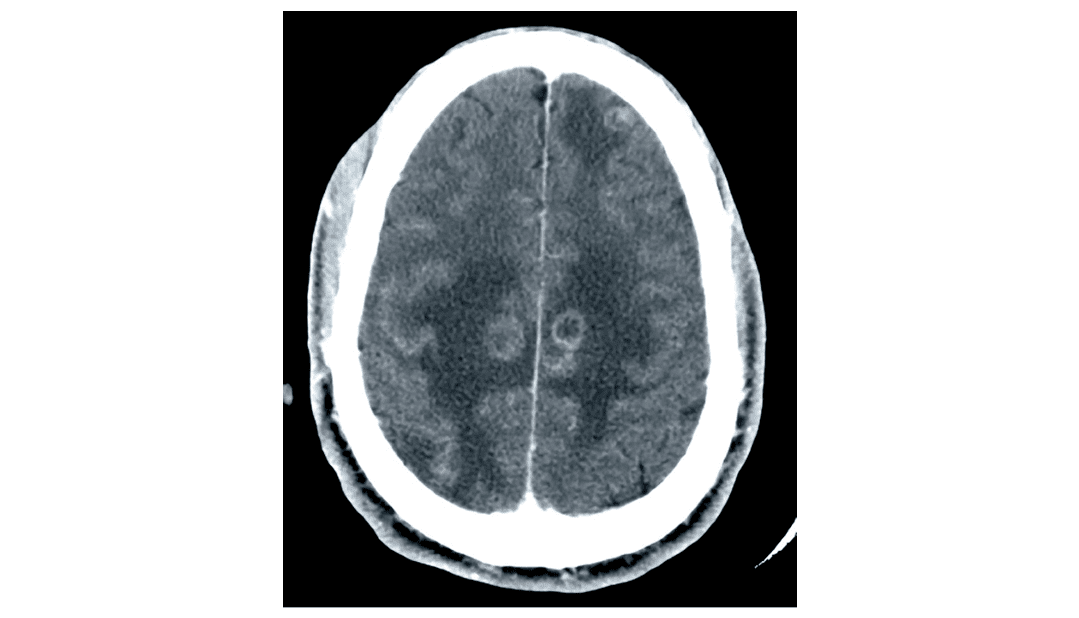

A 35-year-old man is brought to the emergency department after experiencing a seizure. According to his girlfriend, he has had fatigue for the last 3 days and became confused this morning, after which he started having uncontrollable convulsions throughout his entire body. He was unconscious throughout the episode, which lasted about 4 minutes. He has not visited a physician for over 10 years. He has smoked one pack of cigarettes daily for 12 years. His girlfriend admits they occasionally use heroin together with their friends. His temperature is 38.8°C (101.8°F), pulse is 93/min, respirations are 20/min, and blood pressure is 110/70 mm Hg. The lungs are clear to auscultation and examination shows normal heart sounds and no carotid or femoral bruits. He appears emaciated and somnolent. There are multiple track marks on both his arms. He is unable to cooperate for a neurological exam. Laboratory studies show a leukocyte count of 3,000/mm3, a hematocrit of 34%, a platelet count of 354,000/mm3, and an erythrocyte sedimentation rate of 27 mm/h. His CD4+ T-lymphocyte count is 84/mm3 (normal ≥ 500). A CT scan of the head is shown. Which of the following is the most appropriate next step considering this patient's CT scan findings?